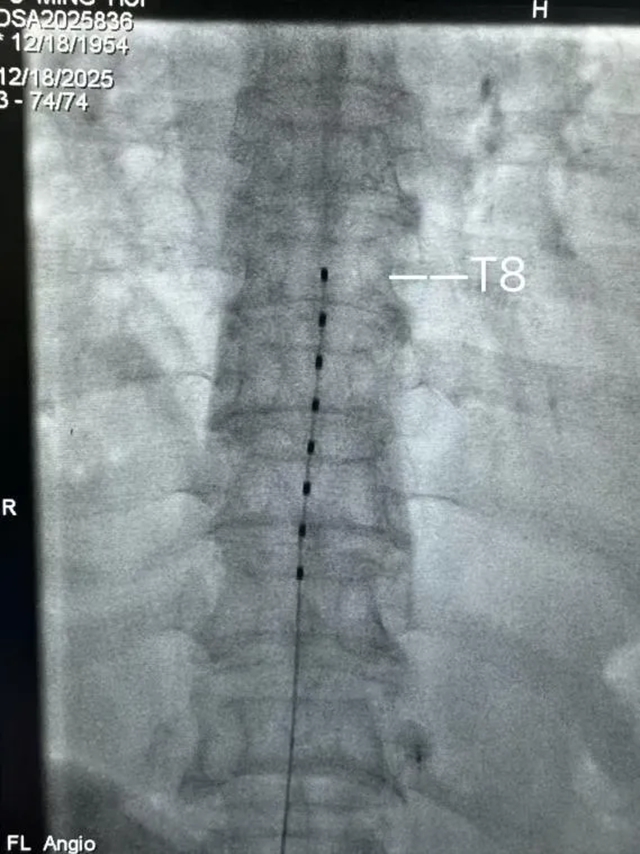

神经电刺激,其实是一种通过电流刺激神经、调节神经功能,从而达到缓解疼痛目的的治疗方法。在付婆婆的案例中,医生采用了单电极植入脊髓后正中的方式,精准覆盖痛处,通过微弱的电流刺激,有效阻断了疼痛信号的传递,实现了疼痛的即时缓解。